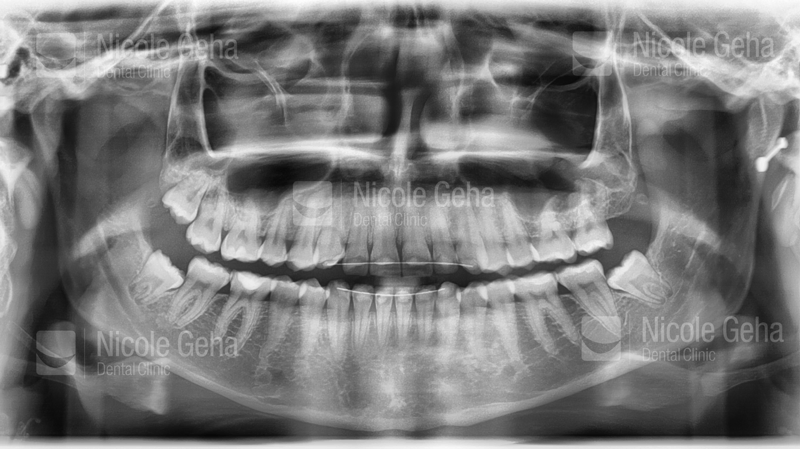

Wisdom teeth may not need to be extracted if they grow in completely and are functional, painless, cavity-free, disease-free and in a hygenic environment with healthy gum tissue. They do, however, require regular, professional cleaning, annual check-ups and periodic X-rays to monitor for any changes.

When a tooth doesn’t fully grow in, it’s “impacted”–usually unable to break through the gums because there isn’t enough room. An impacted wisdom tooth can damage neighboring teeth or become infected. Because it’s in an area that’s hard to clean, it can also invite bacteria that lead to gum disease.